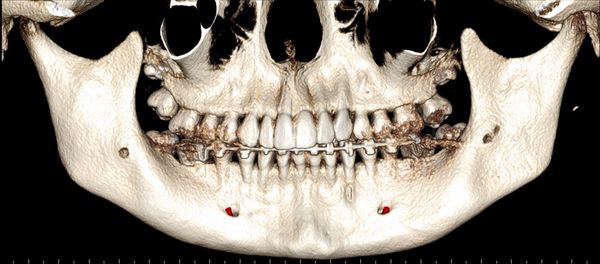

Multiple Mental Foramina - important for surgeries planned in the region, either for dental implants, impacted teeth or periodontal issues

3D Anterior view of the Maxillofacial Skeleton

3D Side view of the Maxillofacial Skeleton